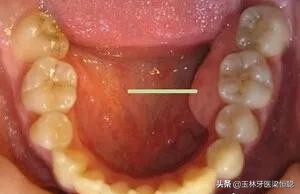

临床上,我们常常遇到患者说“牙龈上鼓了个包,硬硬的”,或镶牙的老人说“牙床压着疼”,通常可能是出现了牙槽骨骨质增生。

口腔内牙槽骨的骨质增生是指牙龈区域的牙槽骨出现骨质增生性突起,在临床上比较常见。

骨质增生的情势多种多样,因所在部位不同而有其各自的特点,在口腔中多表现多圆锥状突起或小骨刺,一般没有明显的临床症状,有时候伴有轻微的疼痛,可以通过X光摄片清晰地辨认骨质增生的部位和增生的程度。

2.针对生理性的骨隆突,一般也不进行治疗。在第三磨牙和双尖牙舌侧牙槽骨的舌侧骨隆突、上颌骨骨隆突、下颌隆突等生理性突起,在进行活动义齿修复时应避开这些地方,以免义齿佩戴后产生压痛。